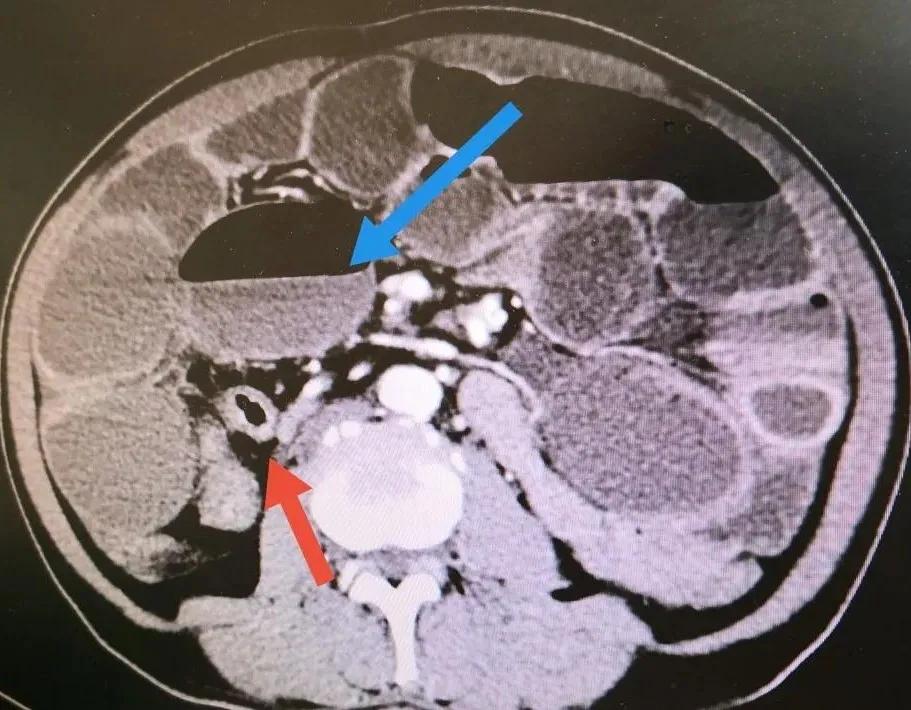

粉红色箭头所示为回盲部肿瘤,已侵犯回肠未端导致全小肠梗阻

蓝色箭头为小肠梗阻后所形成的气液平面,红色箭头所指为空虑的结肠